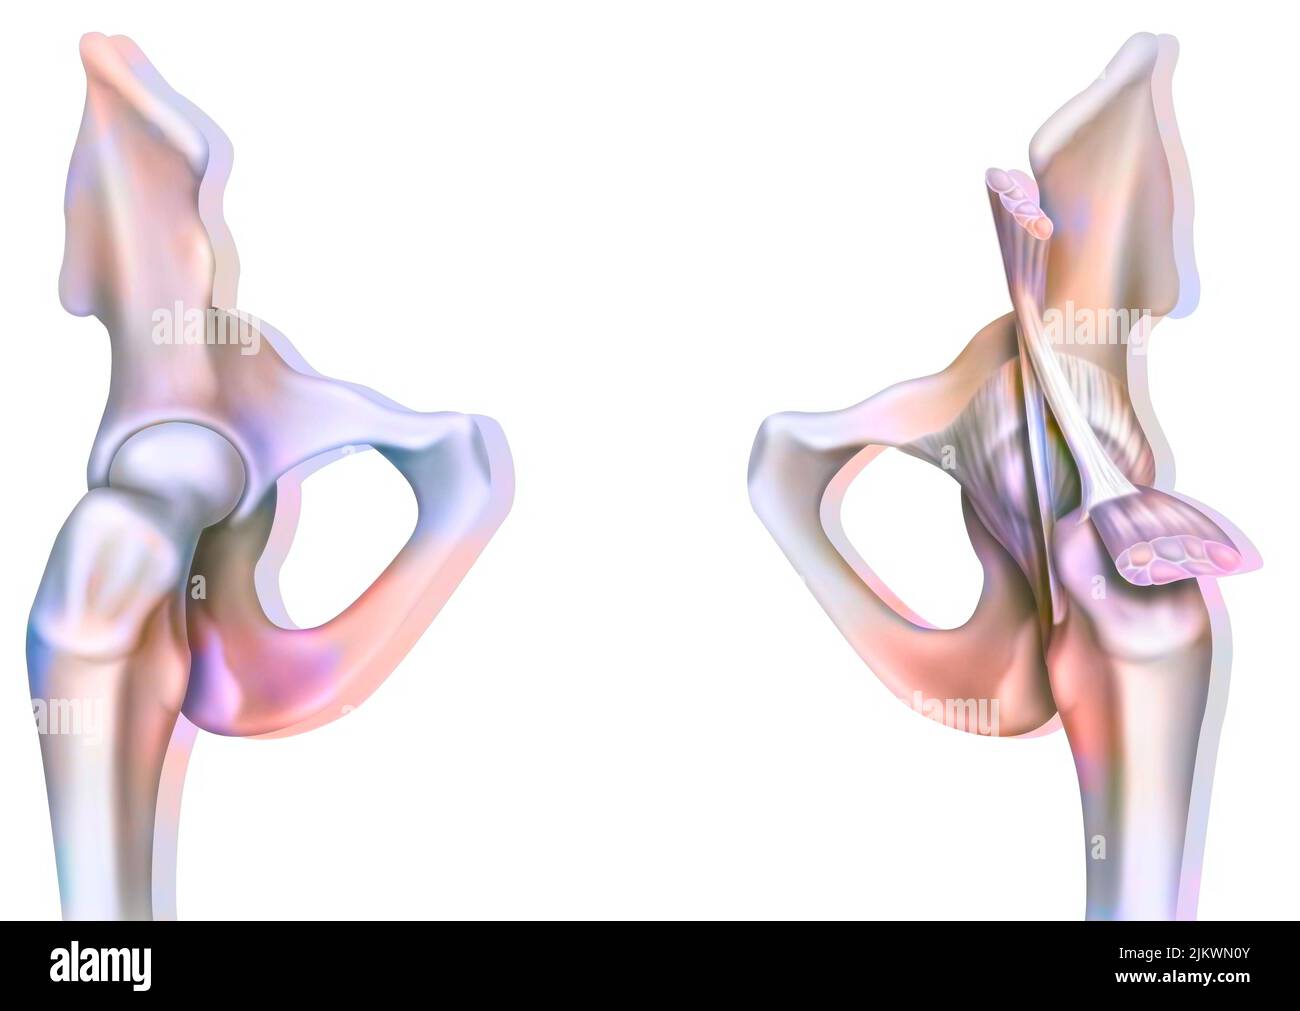

Articulation osseuse de la hanche sans et avec la capsule de l'articulation coxofémorale. Banque D'Imageshttps://www.alamyimages.fr/image-license-details/?v=1https://www.alamyimages.fr/articulation-osseuse-de-la-hanche-sans-et-avec-la-capsule-de-l-articulation-coxofemorale-image476923594.html

Articulation osseuse de la hanche sans et avec la capsule de l'articulation coxofémorale. Banque D'Imageshttps://www.alamyimages.fr/image-license-details/?v=1https://www.alamyimages.fr/articulation-osseuse-de-la-hanche-sans-et-avec-la-capsule-de-l-articulation-coxofemorale-image476923594.htmlRF2JKWMWE–Articulation osseuse de la hanche sans et avec la capsule de l'articulation coxofémorale.

Articulation osseuse de la hanche sans et avec la capsule de l'articulation coxofémorale. Banque D'Imageshttps://www.alamyimages.fr/image-license-details/?v=1https://www.alamyimages.fr/articulation-osseuse-de-la-hanche-sans-et-avec-la-capsule-de-l-articulation-coxofemorale-image476923691.html

Articulation osseuse de la hanche sans et avec la capsule de l'articulation coxofémorale. Banque D'Imageshttps://www.alamyimages.fr/image-license-details/?v=1https://www.alamyimages.fr/articulation-osseuse-de-la-hanche-sans-et-avec-la-capsule-de-l-articulation-coxofemorale-image476923691.htmlRF2JKWN0Y–Articulation osseuse de la hanche sans et avec la capsule de l'articulation coxofémorale.